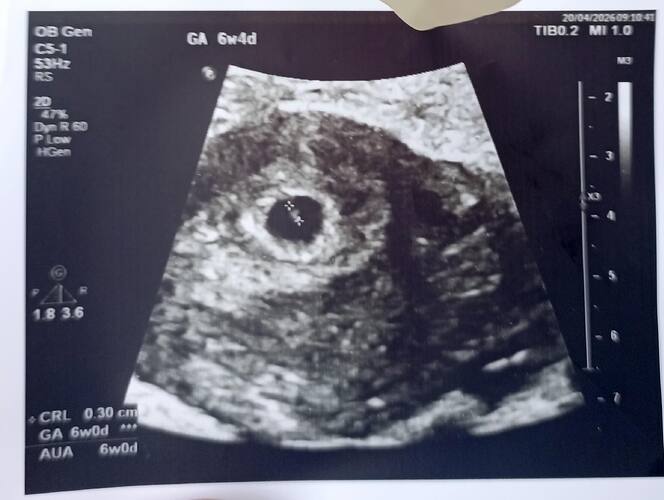

Artık kesin kız diyorum canım ![]()

Kese şekline göre kız bebek diyecegim canim

Kızlarimda kesem öyle değildi

Erkek olması yüksek bence